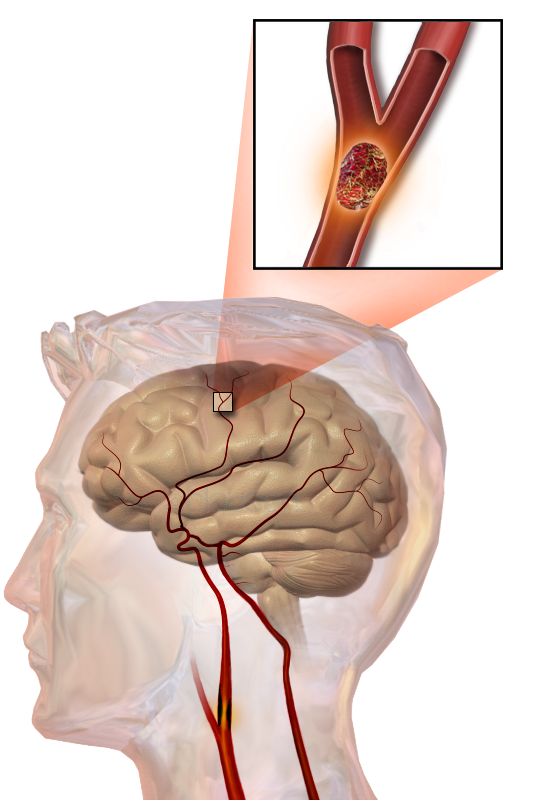

뇌경색(cerebral infarction)은 뇌혈관이 혈전(피떡)이나 색전(혈관을 막는 물질) 등으로 막혀 뇌세포에 산소와 영양 공급이 중단되어 발생하는 질환이다. 뇌경색은 임상적 특징과 여러 진단적 자료에 근거한 TOAST 분류법[293]에 따라 큰 동맥 죽상경화, 심장]-대동맥 색전, 작은 동맥 폐쇄, 기타 원인, 원인 불명으로 분류된다.허혈성 뇌졸중은 혈액 공급 감소로 인해 뇌 조직 기능 장애를 일으킨다. 원인은 다음과 같다.[14][23][24]

혈전성 뇌졸중은 죽상경화성 플라크 주변에 혈전[47](혈액 응고)이 형성되어 발생하는 뇌졸중이다. 동맥 폐쇄가 점진적으로 진행되기 때문에 증상이 나타나는 혈전성 뇌졸중의 발병은 출혈성 뇌졸중에 비해 느리다. 혈전(혈관을 완전히 막지 않더라도)은 떨어져 나가 혈류를 따라 이동하면서 색전성 뇌졸중을 유발할 수 있으며, 이 경우 해당 혈전을 색전이라고 한다.

색전성 뇌졸중은 동맥 내를 이동하는 입자나 잔해인 색전(embolus)에 의한 동맥색전증(동맥의 폐색)을 말한다. 색전은 다른 곳에서 기원하여 동맥 혈류를 따라 이동한다.[54] 색전은 가장 흔하게 혈전이지만, 지방(예: 골절된 뼈의 골수에서), 공기, 암 세포 또는 세균 덩어리(보통 감염성 심내막염에서)를 포함한 다른 여러 물질일 수도 있다.[54]

뇌졸중은 뇌혈류 차단으로 인해 뇌세포가 손상되는 질환이다. 뇌혈류가 차단되면 뇌세포는 에너지를 공급받지 못해 손상된다.

색전성 뇌졸중은 동맥 내를 이동하는 입자나 잔해인 색전(embolus)에 의한 동맥색전증(동맥의 폐색)을 말한다. 색전은 가장 흔하게 혈전이지만, 지방(예: 골절된 뼈의 골수에서), 공기, 암 세포 또는 세균 덩어리(보통 감염성 심내막염에서)등의 여러 물질일 수도 있다.[54]

뇌혈류가 차단되면 뇌세포 활동에 필요한 에너지가 부족해진다. 이로 인해 뇌세포에서는 이온 펌프가 중단되어 뇌세포막의 탈분극이 발생하고, 무기 대사가 촉진된다. 뇌세포막 탈분극은 다량의 신경전달물질을 방출하고, 이들이 산화되면서 독성을 가진 자유 라디칼이 생성된다. 또한 뇌세포막이 탈분극되면 세포 내로 칼슘 이온이 대량 유입되어 지질 분해, 산화 질소 형성, 단백질 분해가 촉진되어 세포 손상이 일어난다.[65]뇌세포에 무기 대사가 촉진되면, 대사 산물인 젖산이 세포 내에 축적된다. 이로 인해 세포질이 산성화되면 철 이온이 유리되어 산화 라디칼 형성이 촉진되고 독성이 유발된다. 결국 이러한 기전들로 인해 뇌세포가 손상되어 대량 괴사가 일어난다.[65]

허혈성 뇌졸중은 뇌의 일부로 가는 혈액 공급이 감소하여 해당 부위의 뇌 조직 기능 장애가 발생하는 현상이다. 이러한 현상이 발생하는 네 가지 이유는 다음과 같다.[65]

허혈성 뇌 조직에서 산소 또는 포도당이 고갈되면 아데노신 삼인산(ATP) 같은 고에너지 인산 화합물 생산이 실패한다. 이는 조직 세포 생존에 필요한 에너지 의존적 과정(예: 이온 펌핑) 실패로 이어진다. 신경세포 손상의 주요 원인은 흥분성 신경전달물질인 글루탐산 방출이다. 뇌졸중은 이온 펌프 작동을 방해하여 막을 가로지르는 이온 기울기를 감소시킨다. 글루탐산 수송체는 방향을 반대로 하여 세포외 공간으로 글루탐산을 방출한다. 글루탐산은 신경 세포 수용체(특히 NMDA 수용체)에 작용하여 칼슘 유입을 생성하고, 이는 세포의 단백질, 지질 및 핵 물질을 분해하는 효소를 활성화한다. 칼슘 유입은 미토콘드리아 기능 장애로 이어질 수 있으며, 이는 에너지 고갈로 더욱 진행되어 프로그램된 세포 사멸로 이어질 수 있다.[69]

허혈성 뇌졸중은 뇌의 일부로 가는 혈액 공급이 차단되어 발생하며, 허혈 연쇄 반응을 일으킨다.[65] 동맥경화증은 혈관 내강을 좁히거나 혈전을 형성하고, 작은 색전을 방출하여 혈액 공급을 방해한다.[66] 색전성 뇌경색은 심장이나 경동맥에서 형성된 색전이 뇌혈관을 막아 발생한다. 뇌혈관이 막히면 뇌는 에너지가 부족해져 혐기성 대사를 이용하게 되는데, 이는 아데노신 삼인산(ATP)을 적게 생성하고 젖산을 생성한다. 젖산은 뇌의 산-염기 균형을 방해하고 세포를 파괴할 수 있다. 허혈 영역은 "허혈성 반그늘"이라고 불린다.[67]